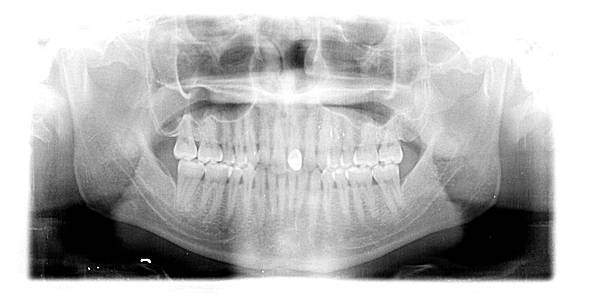

患者年約27歲,男性,於門診中表示:想要做矯正將牙齒排列整齊;經醫師檢查後,建議患者可以做矯正

將戽斗的現象改善,並建議將來需將前牙的假牙重新更換,患者同意了。

原始狀況~~